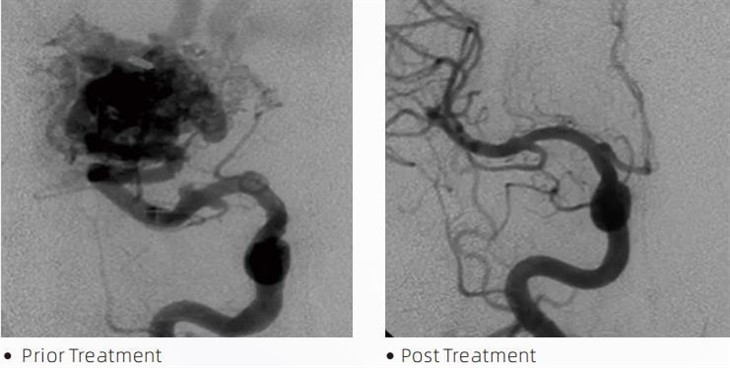

HraunTMembolic lím er lækningatæki sem notað er af inngripandi taugageislafræðingum við lágmarks ífarandi aðgerðir til að meðhöndla sjúkdóma eins og æðagúlp í heila, vansköpun í slagæðum og æxli. Lava embolic límið býður upp á margvíslegan ávinning fyrir læknisfræðinga og sjúklinga hvað varðar öryggi, auðvelda notkun og skilvirkni. Hraun er fær um að loka æðum fljótt og vel. Ferlið felur í sér að límið er sprautað beint inn í æðina þar sem það fjölliðar og harðnar í steypulíkan massa sem fyllir slagæðagúlpið eða vansköpunina. Þá lokar það í raun fyrir blóðflæðið til meinsins, kemur í veg fyrir að það rifni og dregur úr hættu á varanlegum skemmdum eða heilablóðfalli. Hraun inniheldur hraun-12, hraun-18 og hraun-34. Hver samsetning er hönnuð til að mæta sérstökum klínískum þörfum. Lava-18 er staðlað samsetning til almennrar notkunar. Hraun-34 er hárseigjulím fyrir háflæðisílát. Þó að hraun-12 hafi lægri seigju og flæðinlegra, sem gerir ráð fyrir fjarlægum öræðum. Með þessum valkostum geta íhlutunartaugageislafræðingar valið viðeigandi Lava lyfjaform til að tryggja bestu niðurstöður. Einn af merkustu eiginleikum Lava er ólímandi eiginleikar þess. Þetta efni er sérstaklega samsett til að haldast stöðugt þar til það nær marksvæðinu. Þessi eiginleiki þýðir að Lava embolic lím er hægt að setja nákvæmlega í slagæðina og vera þar án þess að festast eða festast við nærliggjandi vef.